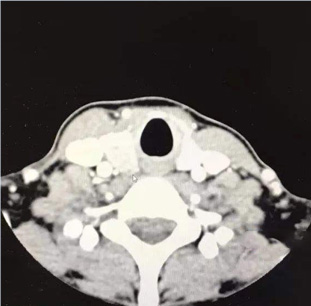

多普勒超声应用

李朕体雕中心应用多普勒超声诊断仪,能够准确检测结节位置、大小、状态,根据检测结果制定结节处理方案。

4D成像技术可以不仅清晰透视求美者胸部结构、乳腺、结缔及血管神经等组织,还能根据乳房的大小、乳头间距、胸部对称度、挺拔程度,为手术方案提供准确数据支持。